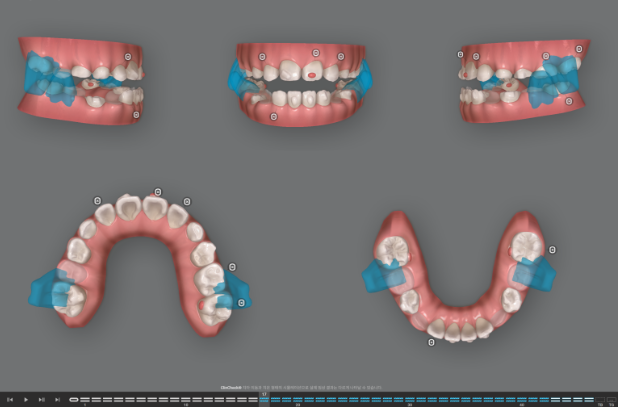

즉 악궁확장이 필요하고 인비절라인 퍼스트로 악궁확장을 동반하여 MA (mandible advance, 하악전진기능) 기능을 이용한 비대칭 치료가 필요합니다.

MA 기능을 활용한 인비절라인퍼스트 어린이 비대칭 교정은 기존 포스팅 참고하시면 좋습니다.

이제 인비절라인퍼스트 치료로 악궁확장, 앞니배열 등을 먼저 진행하여 교합간섭 해소를 도모합니다.

앞니 중심선 개선을 위해 재제작에 들어갔습니다.

23년 12월부터 추가장치를 끼기 시작했습니다.

이후 잔여 공간 분배, 중심선 개선을 위한 MA 기능을 위해 재제작을 한 번 더했습니다.